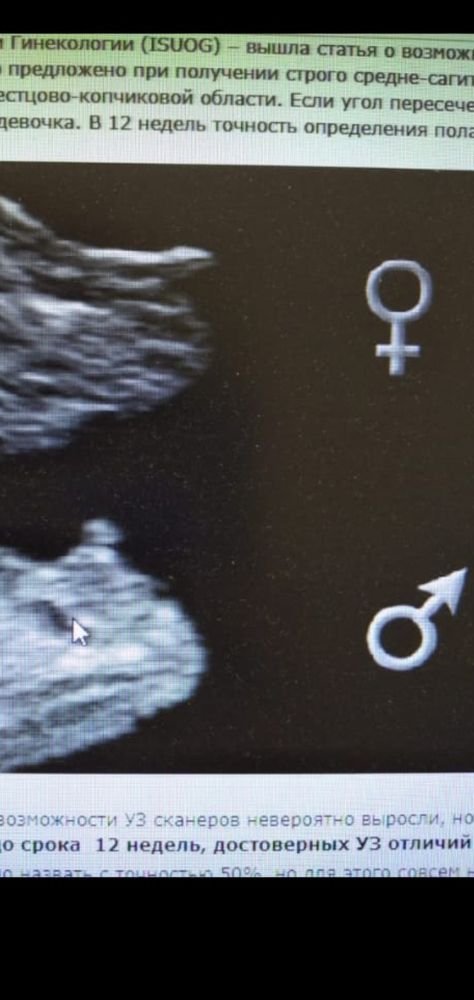

У Вас непонятно по углу наклона девочка, а по самой писюшке вроде мальчик.

Евгения , у меня тоже пока не понятно, врач на узи сказала наклон на девочку, а сама писюшка мальчишки, из-за того что малыш ножки скрещивал наклон писюшки меняется как у девочки становится, сказала ждите второй скрининг🙂

Возможна ли ошибка? Закрашиваю кружок или подождать 2 скрининга?